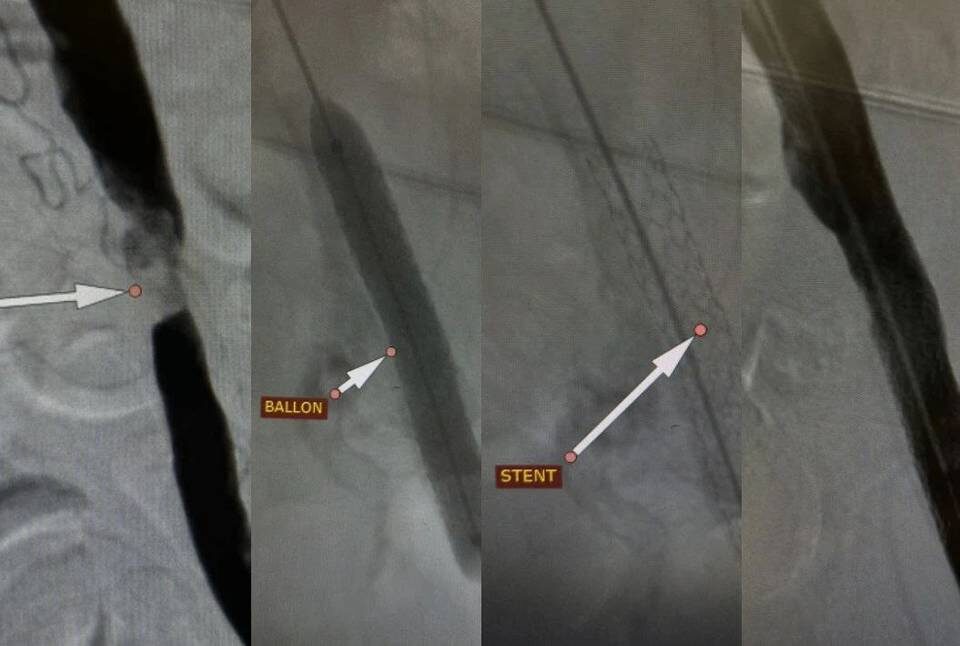

Фото: Комитет здравоохранения Волгоградской области

Процедура проводилась под местной анестезией через небольшой прокол в бедренной артерии. В ходе операции был введен и расширен баллонный катетер, а затем установлен стент для поддержания просвета сосуда.

Мы выполнили стентирование подвздошной артерии, которое позволило быстро нормализовать кровообращение в нижней конечности. Уже спустя сутки пациент смог самостоятельно передвигаться и покинул стационар с рекомендациями для дальнейшего восстановления здоровья, - рассказал заведующий отделением рентгенохирургических методов диагностики и лечения Андрей Легкий.